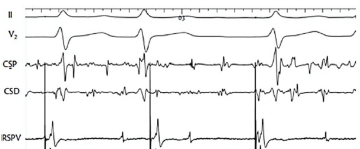

Um engenheiro de 61 anos foi submetido a ablação de fibrilação atrial (FA) paroxística. Os eletrogramas abaixo mostram a leitura dos potenciais elétricos durante ritmo fibrilatório, através de cateter localizado no seio coronário, e a estimulação atrial concomitante através de cateter localizado na veia pulmonar superior direita (VPSD) para avaliar o isolamento da veia pulmonar.

Na imagem acima, II e V2 representam derivações do eletrocardiograma de superfície.

CSP = Seio coronário proximal

CSD = Seio coronário distal (RSPV) = Veia pulmonar superior direita